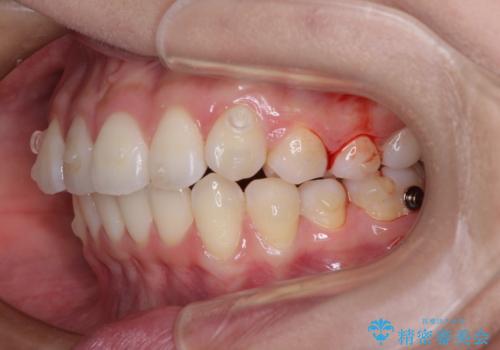

- 前歯のデコボコを治したいとのことで来院された患者様です。

上下顎ともに歯列全体の後方移動とIPR(歯と歯の間を削る)によってデコボコが解消するように設計し、インビザラインにより治療を行うこととしました。